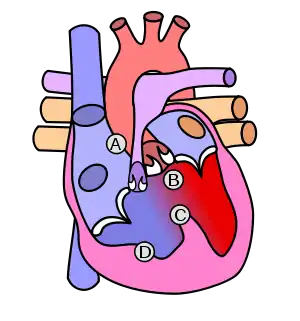

![]() | |

| Diagram of a healthy heart and one with tetralogy of Fallot | |

The cause is typically not known.[5] Risk factors include a mother who uses alcohol, has diabetes, is over the age of 40, or gets rubella during pregnancy.[5] It may also be associated with Down syndrome.[10] Classically there are four defects:[4]

- pulmonary stenosis, narrowing of the exit from the right ventricle

- a ventricular septal defect, a hole between the two ventricles

- right ventricular hypertrophy, thickening of the right ventricular muscle

- an overriding aorta, which allows blood from both ventricles to enter the aorta

Four malformations

"Tetralogy" denotes four parts, here implying the syndrome's four anatomic defects.[2] This is not to be confused with the similarly named teratology, a field of medicine concerned with abnormal development and congenital malformations (including tetralogy of Fallot). Below are the four heart malformations that present together in tetralogy of Fallot:

| Pulmonary Infundibular Stenosis | A narrowing of the right ventricular outflow tract. It can occur at the pulmonary valve (valvular stenosis) or just below the pulmonary valve (infundibular stenosis). Infundibular pulmonic stenosis is mostly caused by the overgrowth of the heart muscle wall (hypertrophy of the septoparietal trabeculae),[29] however, the events leading to the formation of the overriding aorta are also believed to be a cause. The pulmonic stenosis is the major cause of the malformations, with the other associated malformations acting as compensatory mechanisms to the pulmonic stenosis.[30] The degree of stenosis varies between individuals with TOF and is the primary determinant of symptoms and severity. This malformation is infrequently described as sub-pulmonary stenosis or subpulmonary obstruction.[31] |

| Overriding aorta | An aortic valve with biventricular connection, that is, it is situated above the ventricular septal defect and connected to both the right and the left ventricle. The degree to which the aorta is attached to the right ventricle is referred to as its degree of "override." The aortic root can be displaced toward the front (anteriorly) or directly above the septal defect, but it is always abnormally located to the right of the root of the pulmonary artery. The degree of override is extremely variable, with 5-95% of the valve being connected to the right ventricle.[29] |

| Ventricular septal defect (VSD) | A hole between the two bottom chambers (ventricles) of the heart. The defect is centered around the most superior aspect of the ventricular septum (the outlet septum), and in the majority of cases is single and large. In some cases, thickening of the septum (septal hypertrophy) can narrow the margins of the defect.[29] |

| Right ventricular hypertrophy | The right ventricle is more muscular than normal, causing a characteristic boot-shaped (coeur-en-sabot) appearance as seen by chest X-ray. Due to the misarrangement of the external ventricular septum, the right ventricular wall increases in size to deal with the increased obstruction to the right outflow tract. This feature is now generally agreed to be a secondary anomaly, as the level of hypertrophy tends to increase with age.[32] |